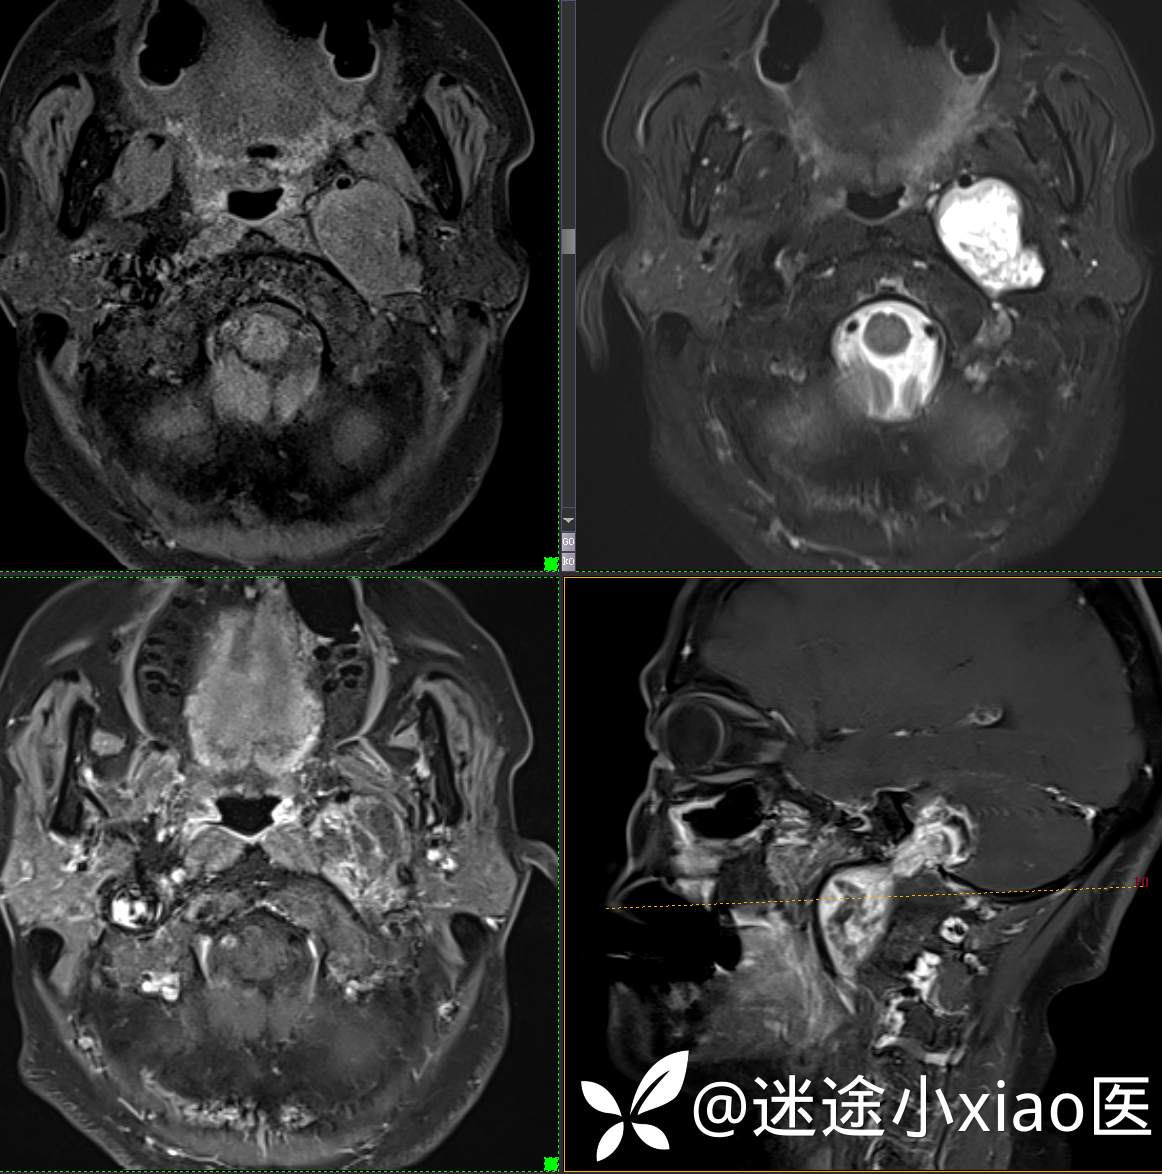

头颈组17:颈静脉孔区占位,副神经节瘤?神经鞘瘤?脑膜瘤?

患者性别:女

患者年龄:57岁

主 诉:  声音嘶哑进食困难伴左侧颌部麻木半年

现病史:  【患者半年前无明显诱因出现声音嘶哑,进食困难,只能进食糊状食物,伴有恶心呕吐,无明显头痛头晕,未加重视。